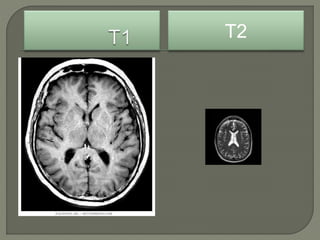

Т1 Т2